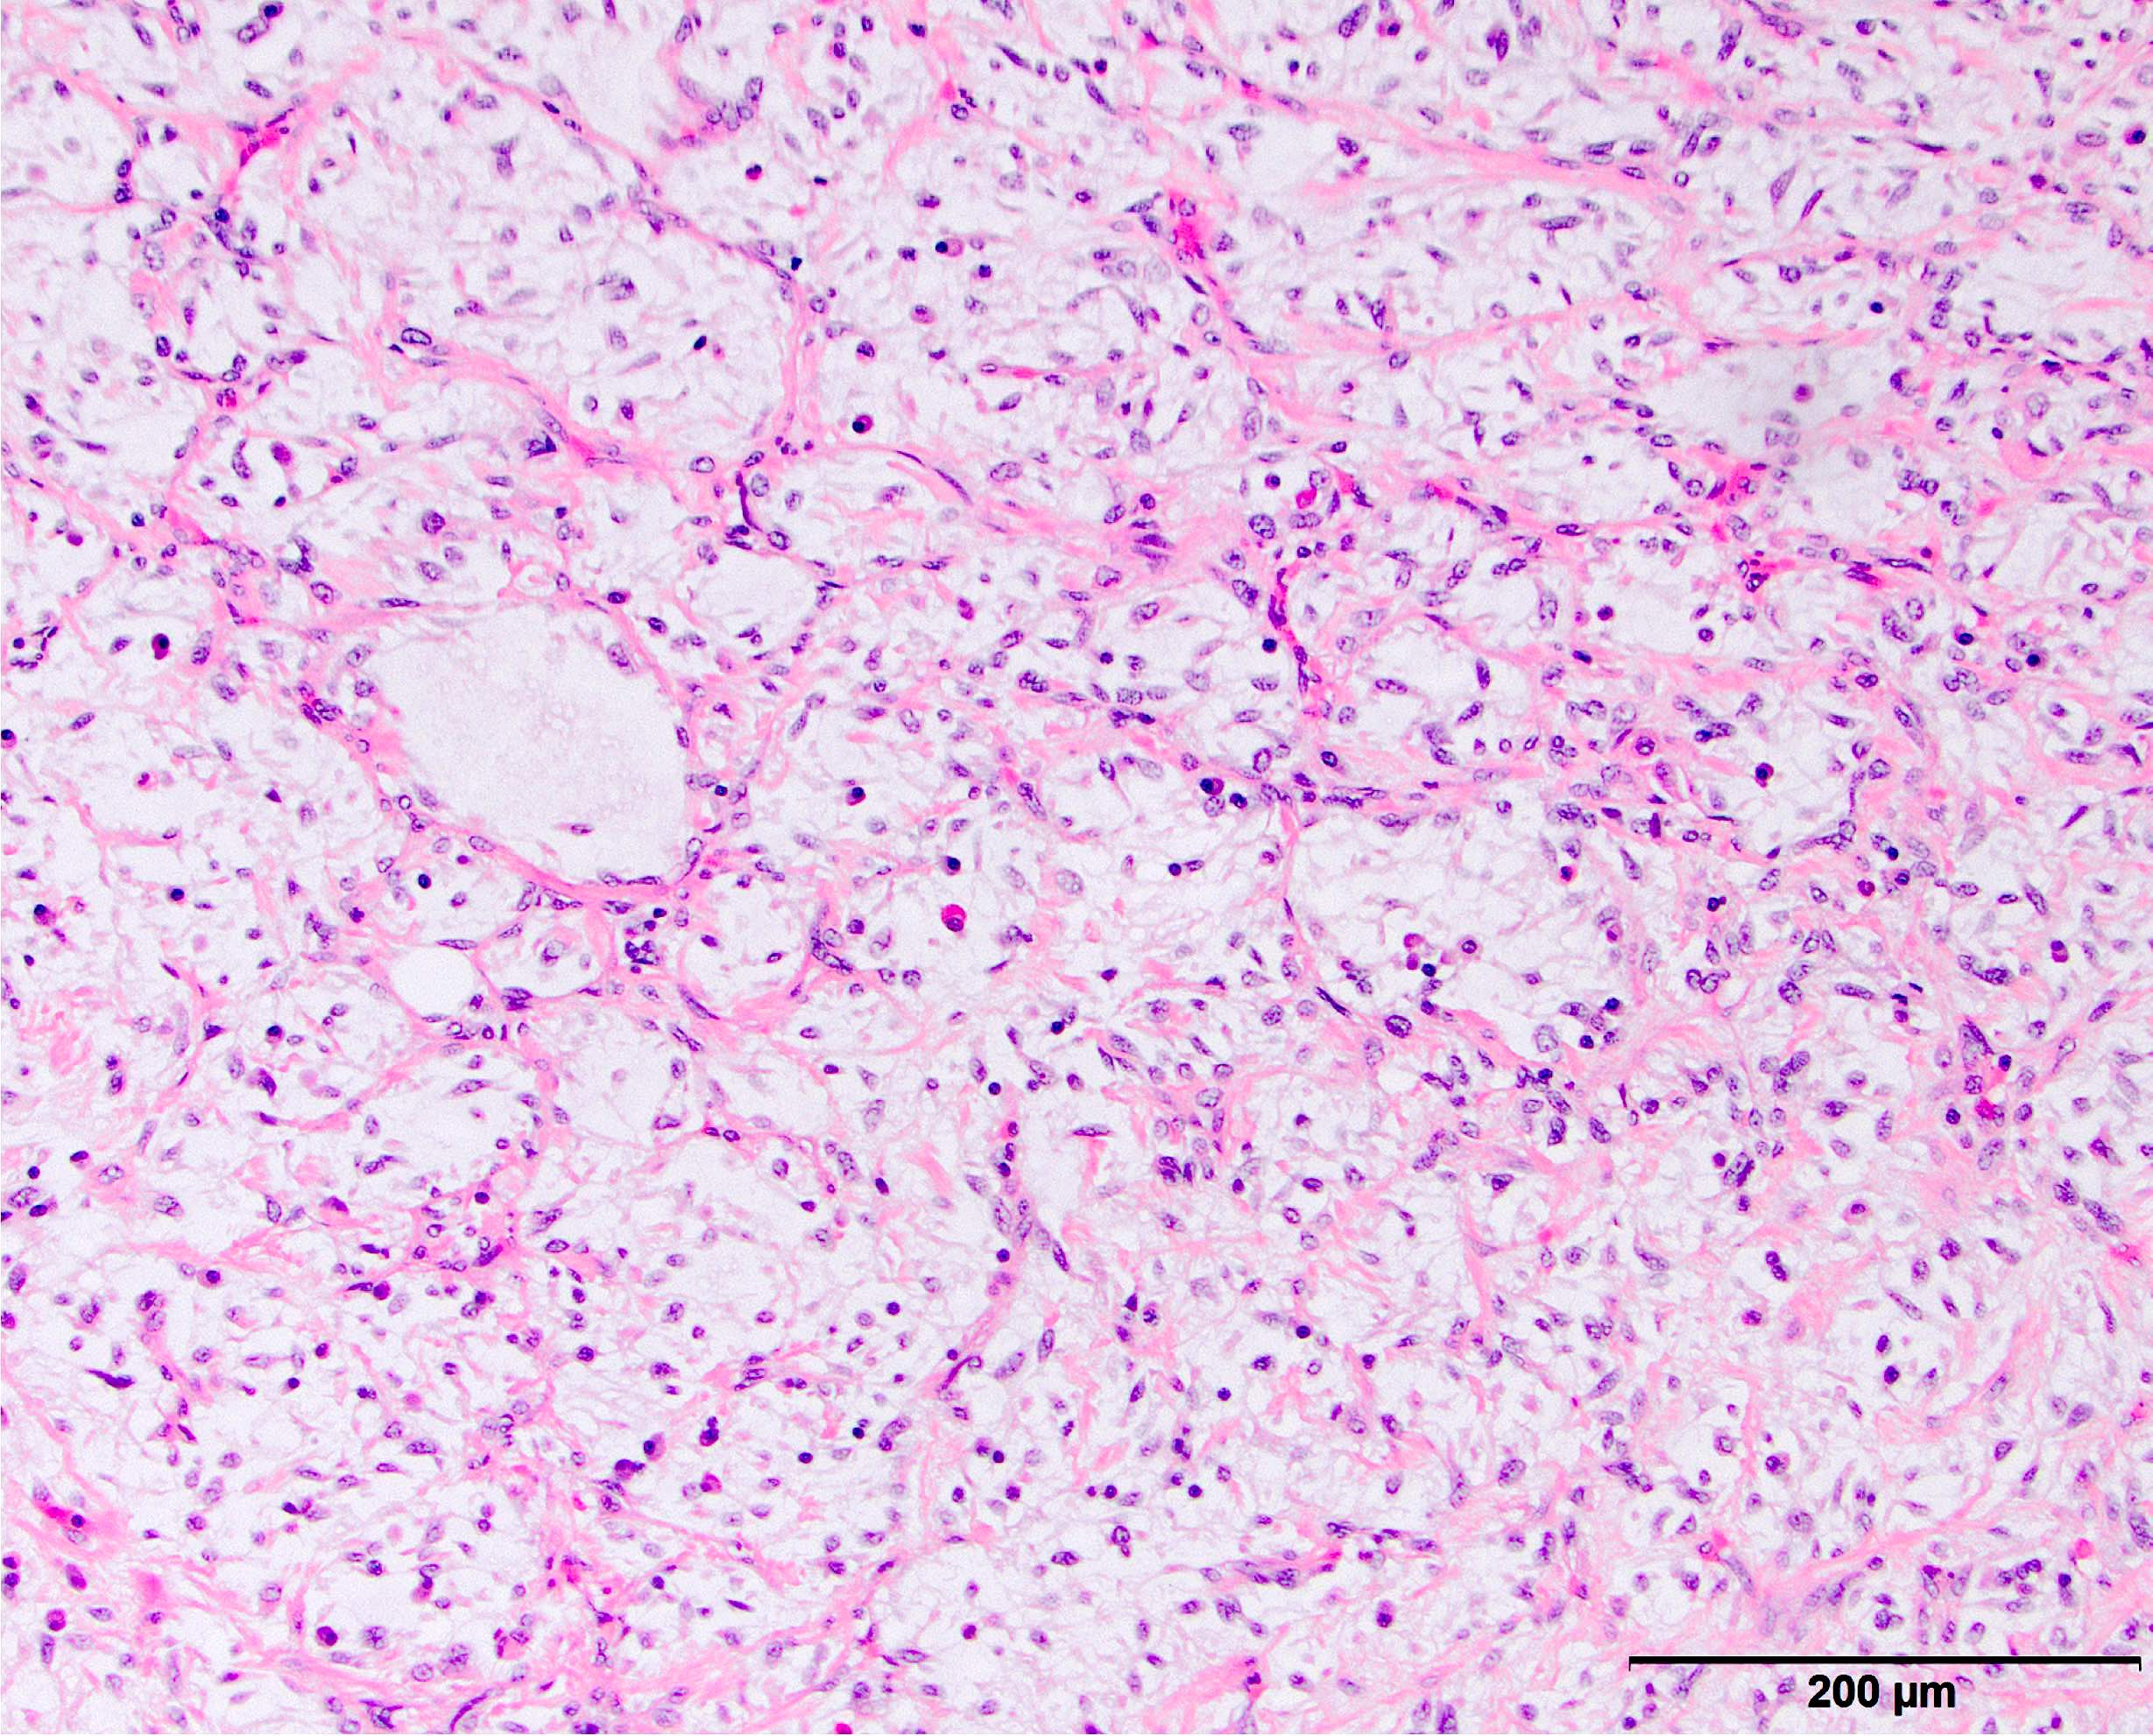

- High grade dedifferentiated liposarcoma

- Dedifferentiated component is a cellular and typically a nonlipogenic sarcoma with significant pleomorphism

- Often resembles malignant fibrous histiocytoma (MFH), now referred to as undifferentiated pleomorphic sarcoma (UPS), with short fascicles of pleomorphic spindle cells associated with mixed inflammatory infiltrate

- Myxoid liposarcoma-like morphologic features may exist in a subset of cases (often with coexisting amplification of DDIT3) and are important to recognize as a unique histologic pattern of dedifferentiated liposarcoma to avoid misclassification as myxoid liposarcoma (Mod Pathol 2019;32:585)

Microscopic (histologic) images

Contributed by Michael R. Clay, M.D. and AFIP